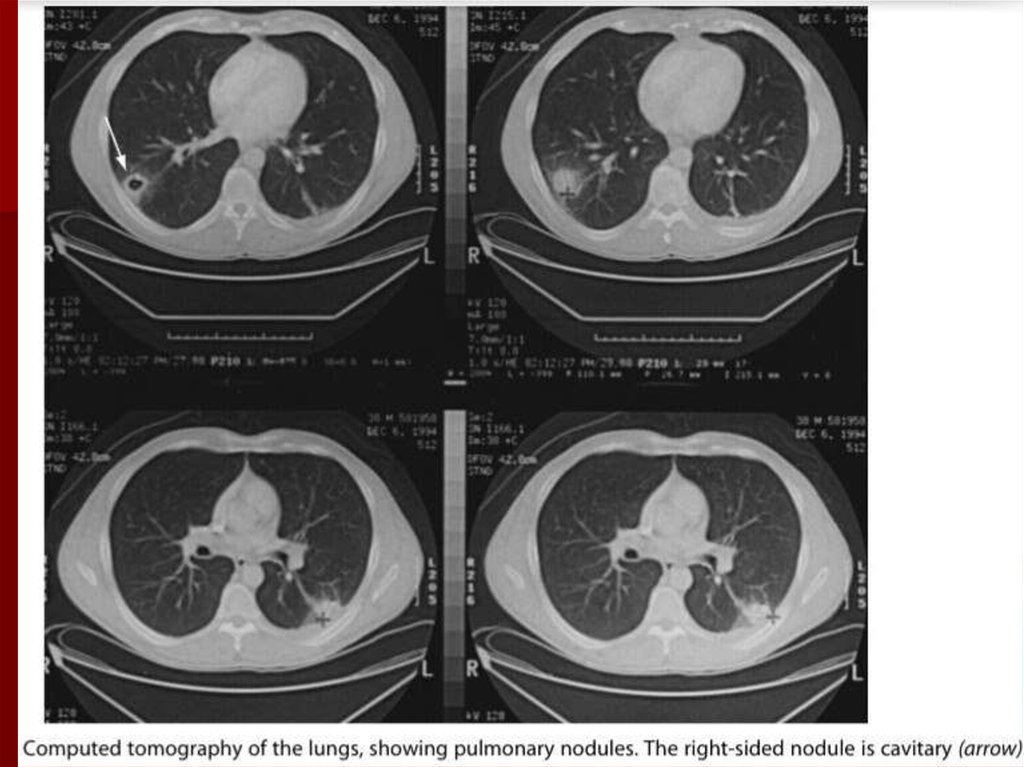

39. Диагностика